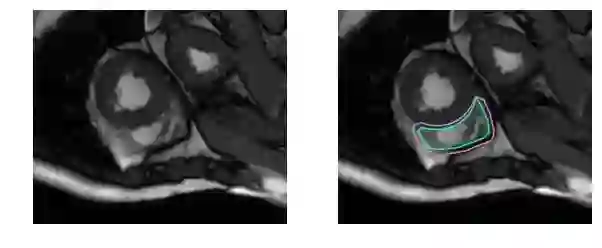

再困难一点:

而对于未训练过的肉眼,右心室区域是这样的: